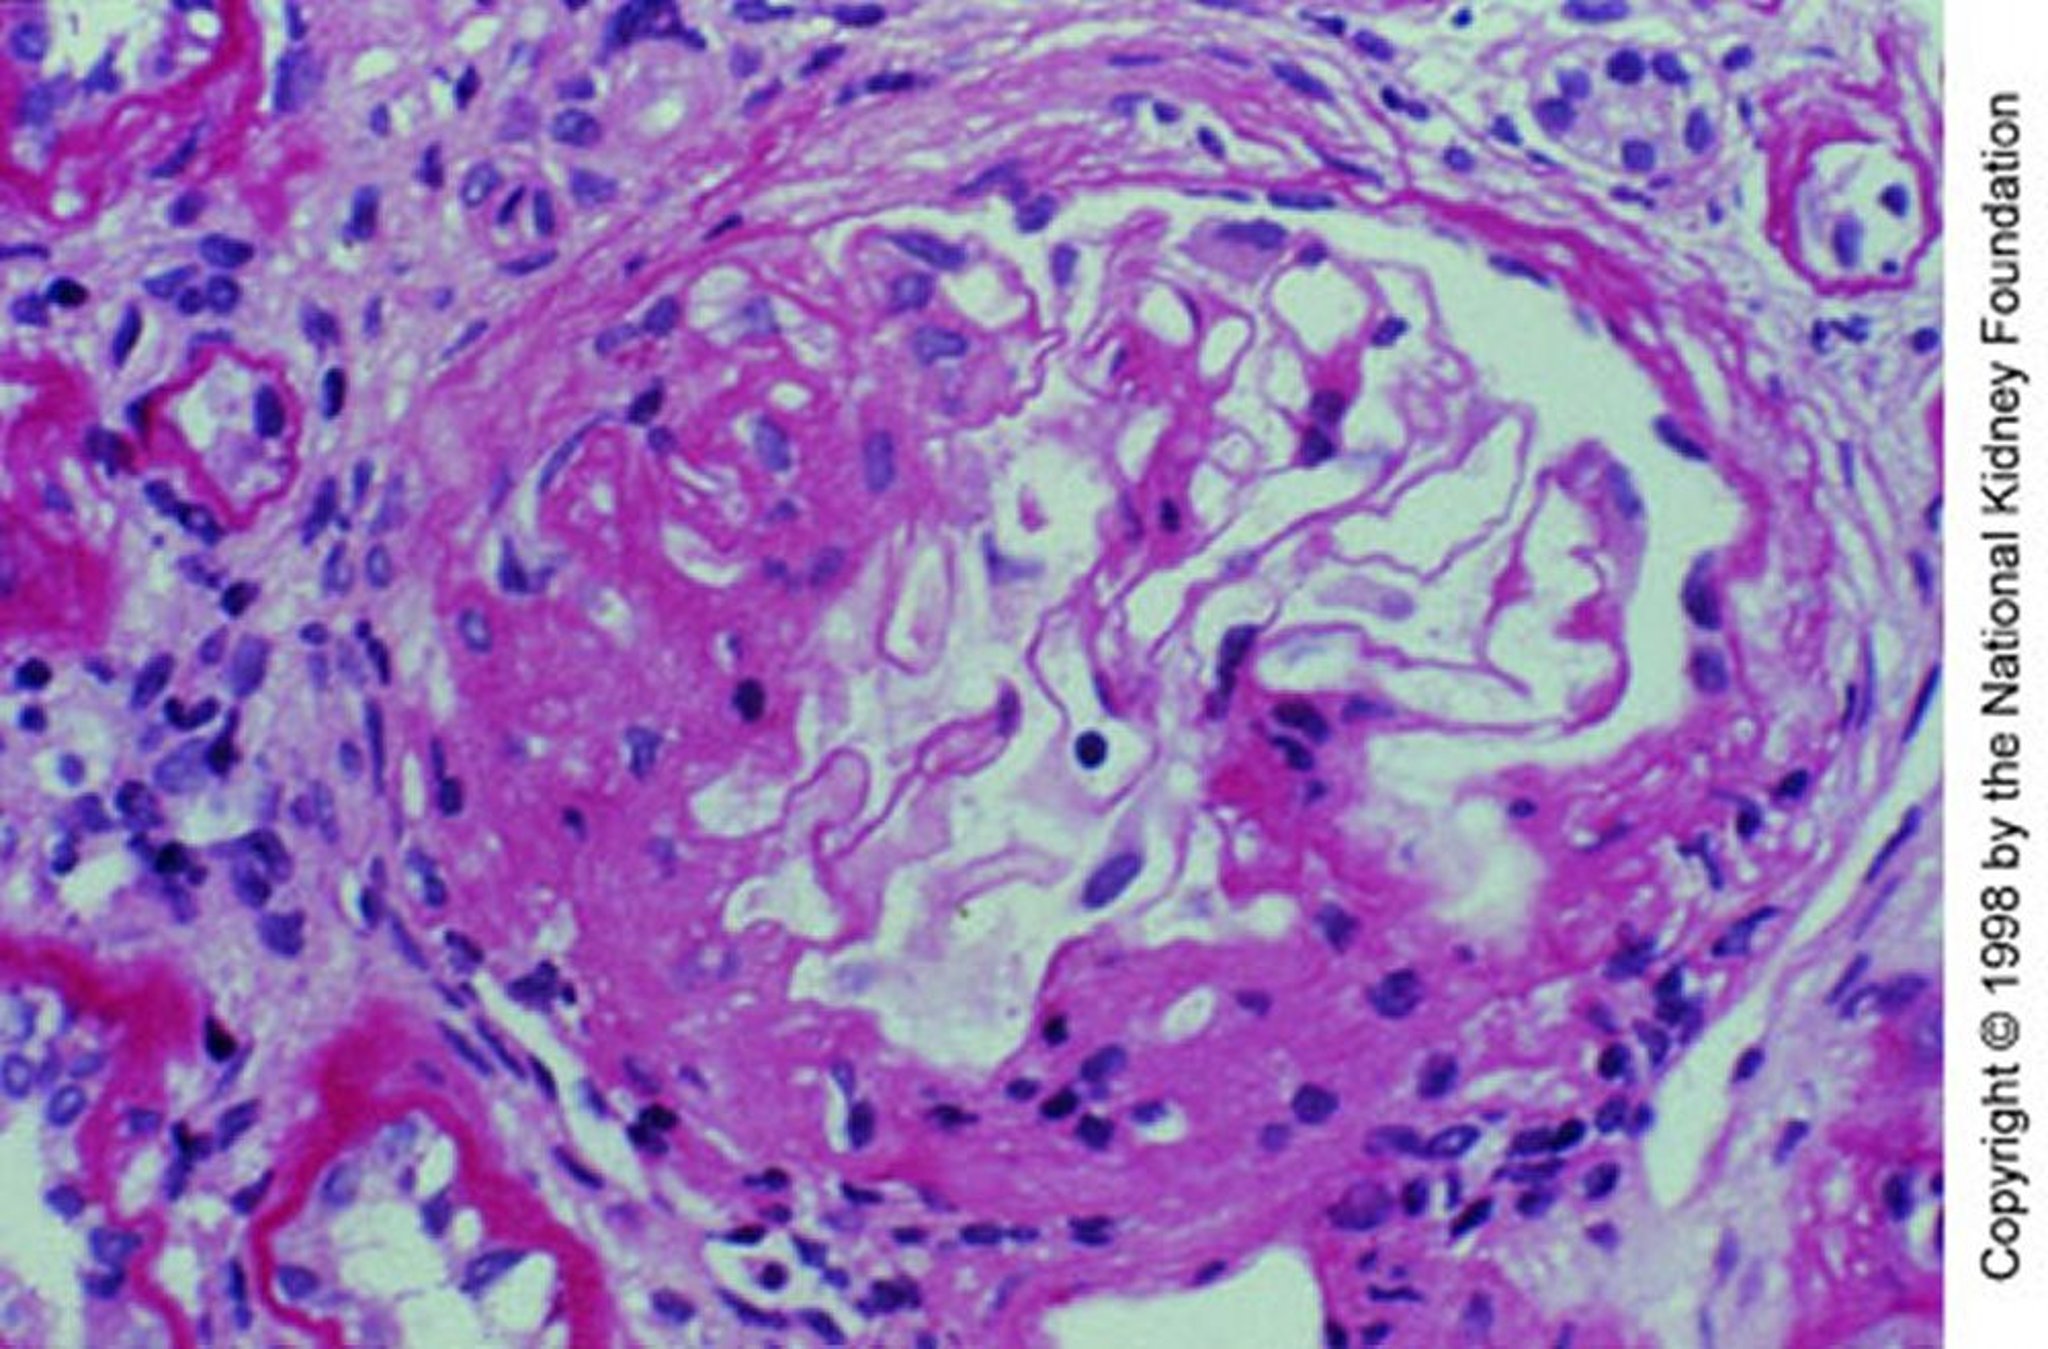

Image provided by Agnes Fogo, MD, and the American Journal of Kidney Diseases' Atlas of Renal Pathology (see www.ajkd.org).

腎生検では,巣状の分節性増殖性病変または壊死性病変を伴う拡大したメサンギウム領域内に,IgAと補体(C3)の顆粒状沈着が蛍光抗体染色法で示される。重要な点として,メサンギウム領域のIgA沈着は非特異的であり,他の多くの疾患でも起こり,具体的にはIgA血管炎,肝硬変,炎症性腸疾患,セリアック病,乾癬,HIV感染症,肺癌,いくつかの全身性リウマチ性疾患などがある。